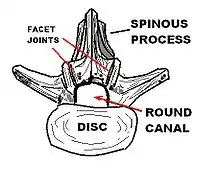

Spinal stenosis may be congenital (rarely) or acquired (degenerative), overlapping changes normally seen in the aging spine.[6][7] Stenosis can occur as either central stenosis (the narrowing of the entire canal) or foraminal stenosis (the narrowing of the foramen through which the nerve root exits the spinal canal). Severe narrowing of the lateral portion of the canal is called lateral recess stenosis. The ligamentum flavum (yellow ligament), an important structural component intimately adjacent to the posterior portion of the dural sac (nerve sac) can become thickened and cause stenosis. The articular facets, also in the posterior portion of the bony spine can become thickened and enlarged, causing stenosis. These changes are often called "trophic changes" or "facet trophism" in radiology reports. As the canal becomes smaller, resembling a triangular shape, it is called a "trefoil" canal.